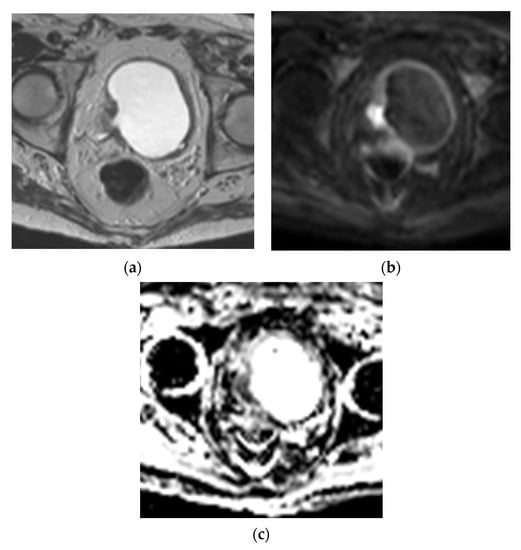

5.2. Magnetic Resonance Imaging (MRI)

- Panebianco, V.; Narumi, Y.; Altun, E.; Bochner, B.H.; Efstathiou, J.A.; Hafeez, S.; Huddart, R.; Kennish, S.; Lerner, S.; Montironi, R.; et al. Multiparametric Magnetic Resonance Imaging for Bladder Cancer: Development of VI-RADS (Vesical Imaging-Reporting and Data System). Eur. Urol. 2018, 74, 294–306. [Google Scholar] [CrossRef] [PubMed]

| DWI/ADC score Diffusion weighted category (DW) | Tumor is hyperintense on DWI, hypointense on ADC Muscularis propria is intermediate SI on DWI Stalk and inner layer are low SI on DWI |

| DW 1 | Intact intermediate SI muscularis propria on DWI Lesion < 1 cm |

| DW 2 | Intact intermediate SI muscularis propria on DWI Lesion > 1 cm |

| DW 3 | Lack of category 2 findings with no clear disruption of muscularis propria |

| DW 4 | Tumor (high SI on DWI/low SI on ADC) extends into muscularis propria |

| DW 5 | Tumor (high SI on DWI/low SI on ADC) extends to entire bladder wall and extravesical fat |